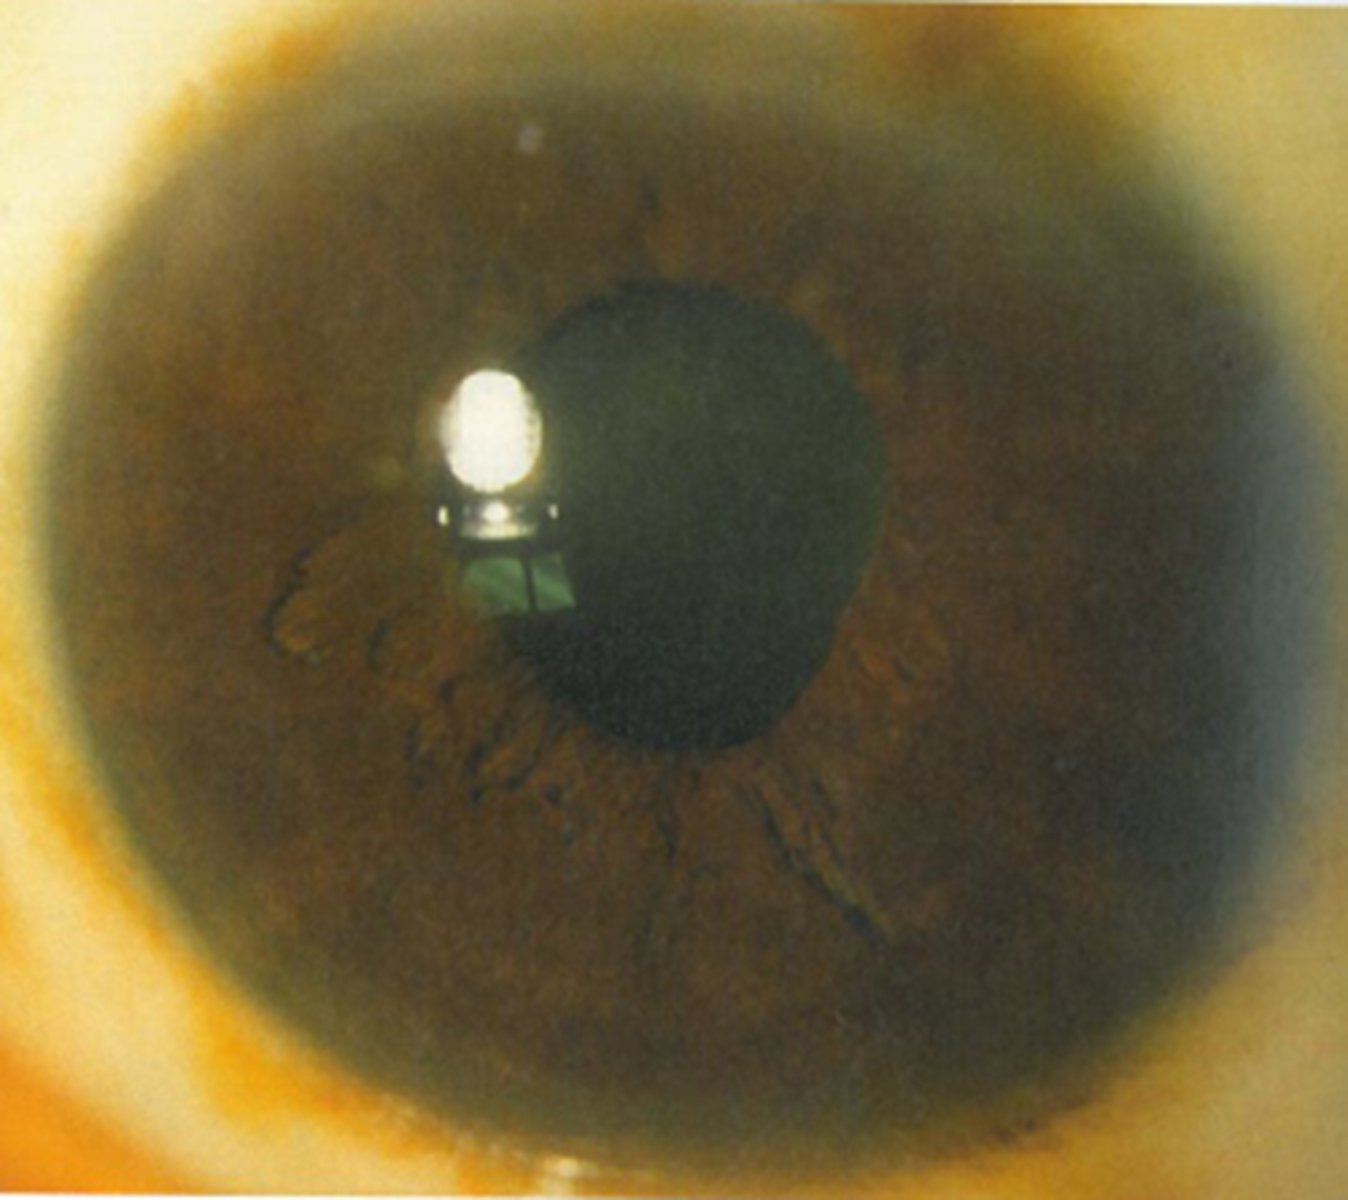

Ex) Based on the result of this 0.125% pilocarpine denervation supersensitivity test, which eye has the tonic pupil?

OD bc this is the diseased eye that is starved for ACh, so it will respond to dilute pilocarpine